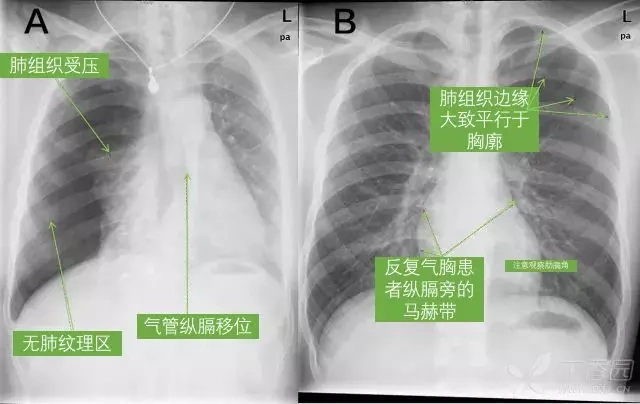

超详细胸片教学,不信你还学不会!